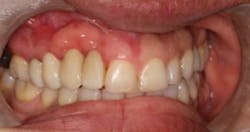

The patient presented to restore the implant six months later with a predicted large vertical and horizontal tissue defect (figure 3). The implant was restored with gingival ceramics to compensate for the ridge defect (figure 4).

The patient was very pleased with the final outcome (figure 5), even though this case certainly would not be considered an esthetic success. Because of the patient’s concerns and low smile line (figure 6), this case was completed six months postextraction and in a cost-efficient manner.